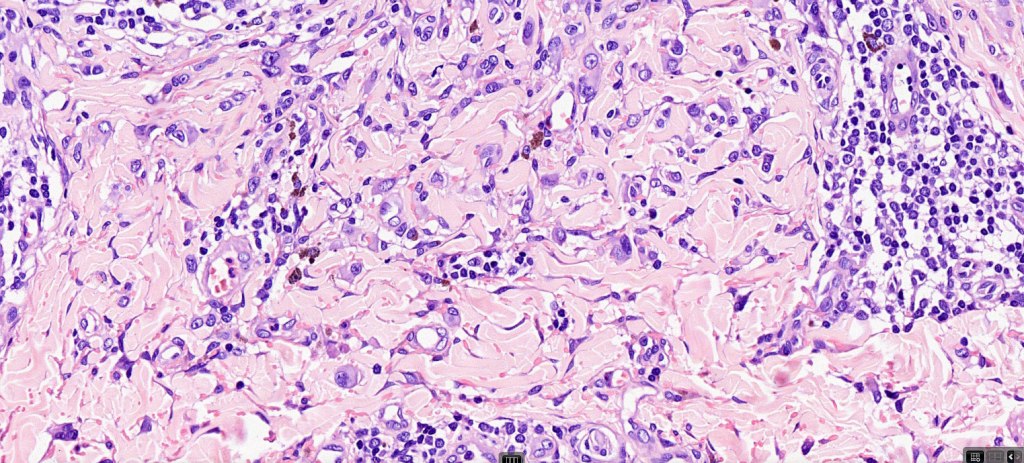

Combined common melanocytic nevus & BAP1-inactivated melanocytoma